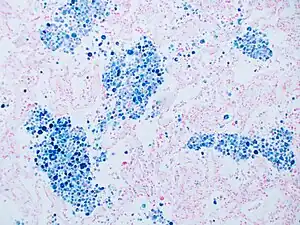

Stain for iron

Prussian blue is a common histopathology stain used by pathologists to detect the presence of iron in biopsy specimens, such as in bone marrow samples. The original stain formula, known historically (1867) as "Perls Prussian blue" after its inventor, German pathologist Max Perls (1843–1881), used separate solutions of potassium ferrocyanide and acid to stain tissue (these are now used combined, just before staining). Iron deposits in tissue then form the purple Prussian blue dye in place, and are visualized as blue or purple deposits.[39]